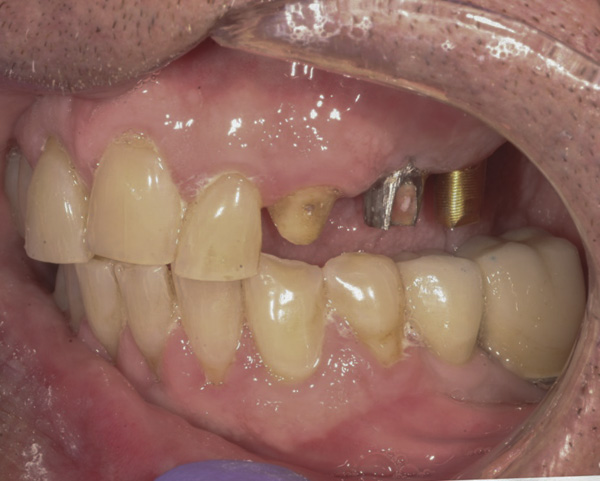

(Note: A separate but similar type of case shown in Figure 4 and Figure 5 further illustrates intraoral abutment re-preparation.)

Figure 4 Following osseointegration of an implant at No. 12, recession was observed at the fixture-level impression stage of No. 13; it was decided to re-prepare the margins of the CAD/CAM custom abutment of implant No. 12. Retraction cord was placed prior to preparation to avoid tissue injury and improve visibility of both tooth No. 11 and the implant custom abutment margin. As expected, recession was greater along the distal side of abutment No. 12, adjacent to the healed extraction/newer implant site.

Figure 4

Figure 5 Newly placed custom abutment on No. 13 with the previously re-prepared abutment at No. 12. No new recession has occurred since the case was completed more than 3 years ago.

Figure 5